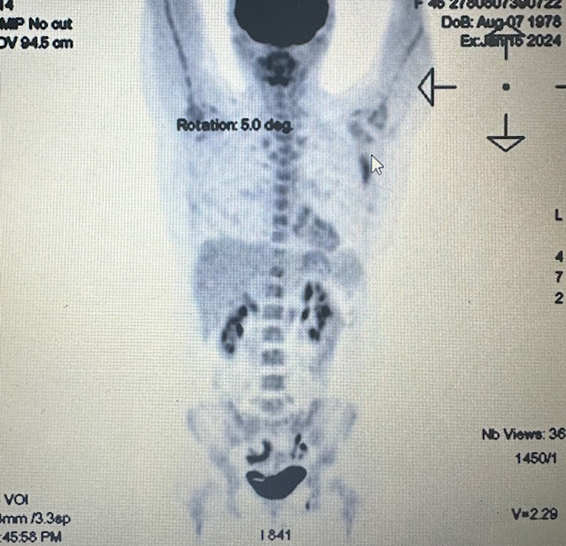

PET/CT revealsactive metabolic changes located around prosthetic implant in the right breast (Figure 4).

Figure 4: Active metabolic changes located around prosthetic implant in the right breast on PET/CT